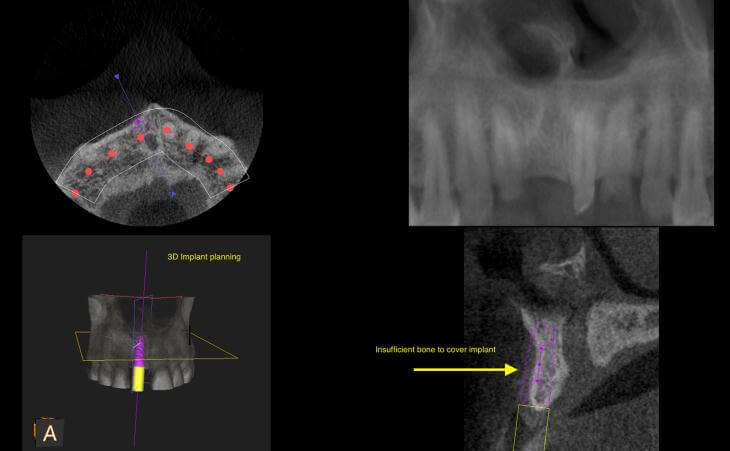

This 19 year old female was born with missing lateral teeth #7 and #10. She had a very resorbed bony areas in her upper jaw where the missing teeth were supposed to be. A CT scan was done. Then a bone regeneration graft was placed and 4 months of healing went by. A New Ct scan was taken to plan the implant placement. Implants were placed into the newly formed bone successfully.